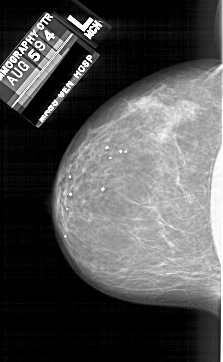

A_1689_1.LEFT_CC

LEFT_CC LINES 5791 PIXELS_PER_LINE 3556 BITS_PER_PIXEL 12 RESOLUTION 43.5 NON_OVERLAY